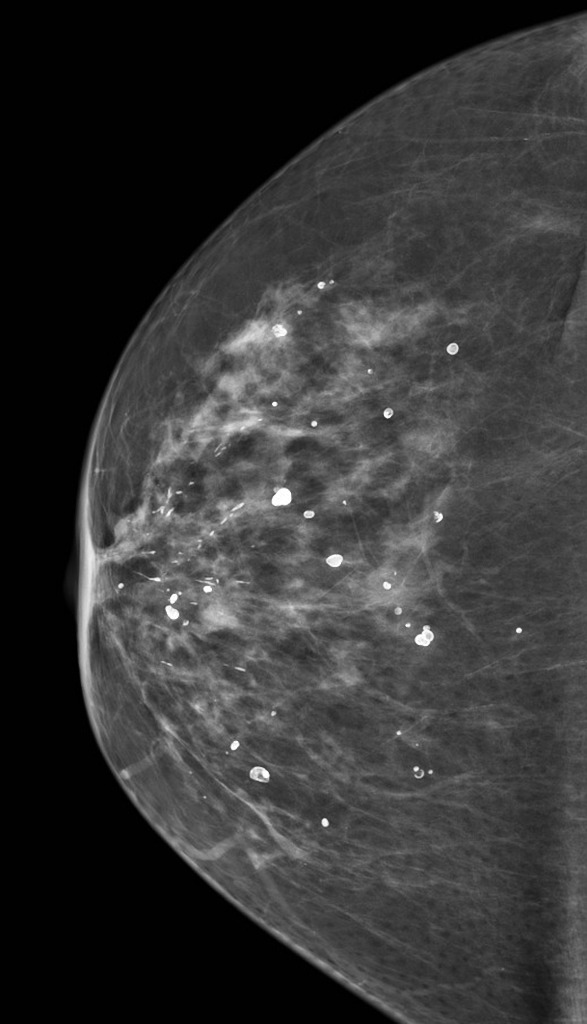

유방촬영으로 ‘석회화’가 발견되는 경우가 있습니다. 유방 석회화는 유방촬영 사진에서 소금 가루처럼 하얀 점들이 보이는 것을 말합니다. 유방 미세 석회화 라고도 합니다. 이는 지방세포가 변해서 생기거나 염증이나 물혹 안에서 칼슘이 뭉쳐져 생겨날 수도 있습니다.

양성석회화는 저절로 없어지는 것이 대부분 이기도 하지만 악성석회화는 암세포 일부가 죽은 후 변성돼 생기기 때문에 유방암의 징후로 볼 수도 있습니다.

석회화는 모양을 보면 암 여부를 어느 정도 구별할 수 있습니다. 물론 모양만으로 암 여부를 명확히 구별할 수 없기 때문에 조직검사를 실시해야 합니다.